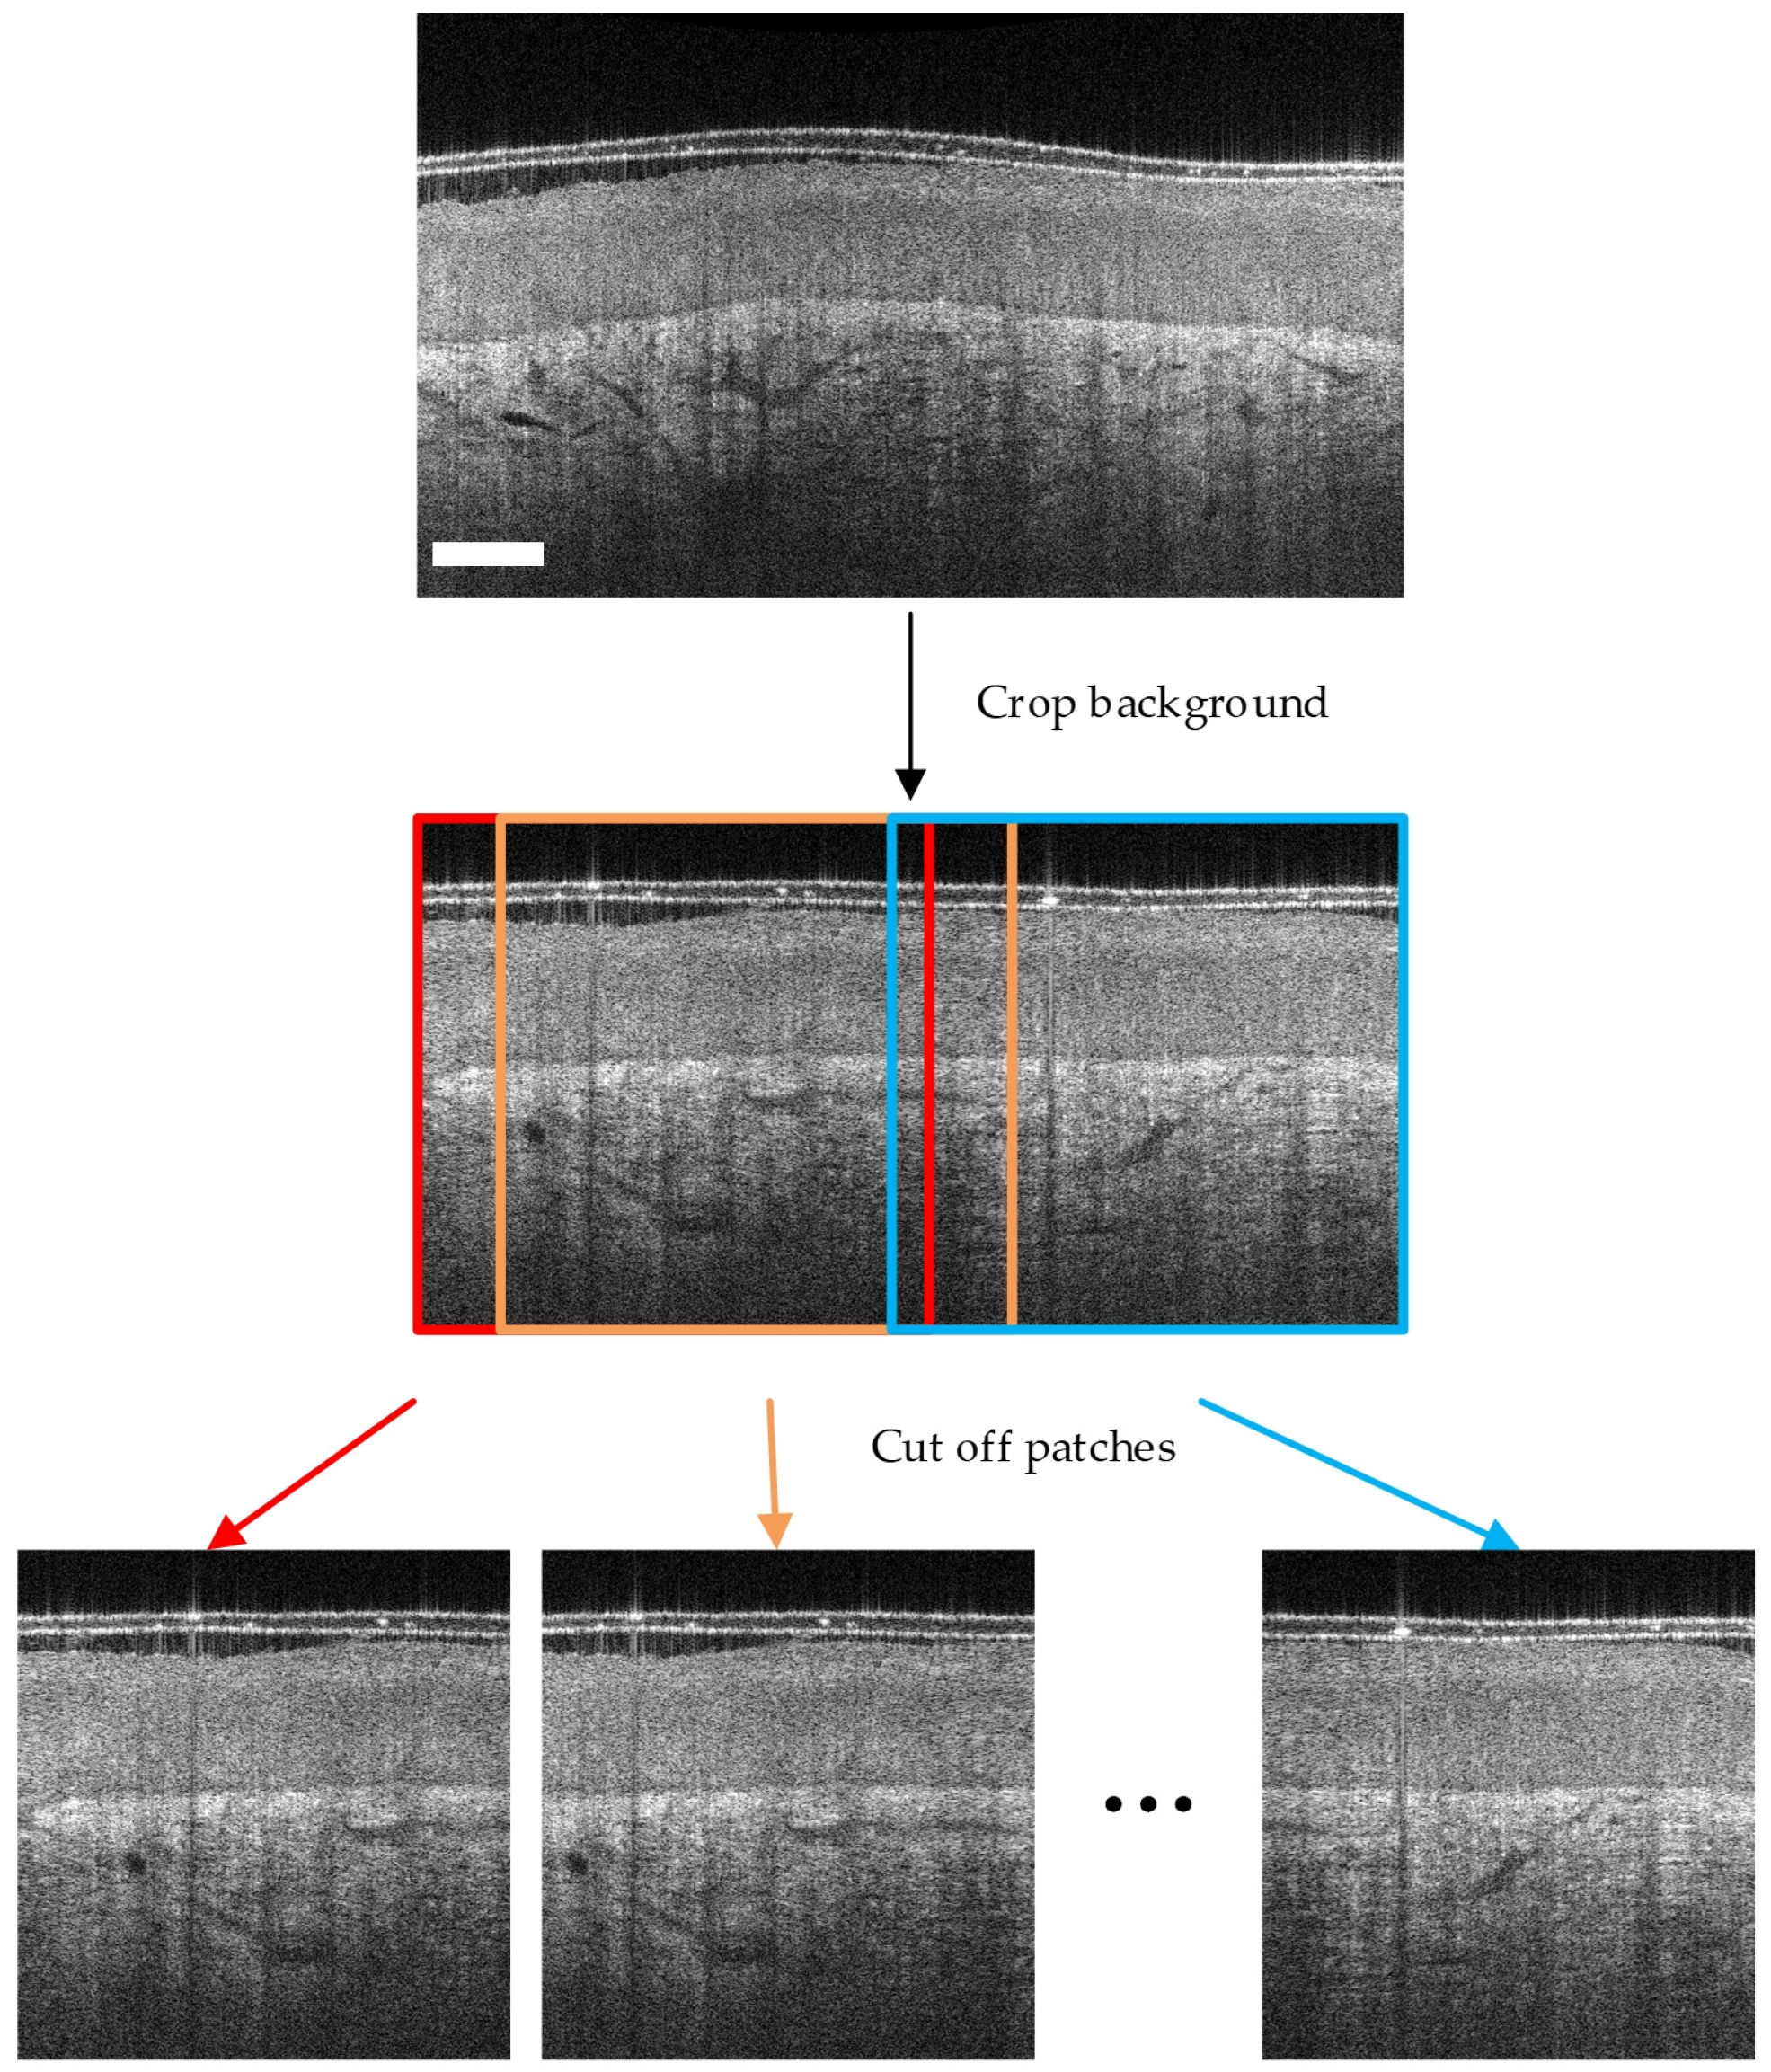

High-resolution cervical OCT volumes are too large to efficiently train deep learning (DL) models based on convolutional neural networks (CNNs). Figure A1 presents the extraction process of OCT images of 600 × 600 pixels from a frame of an entire OCT volume (size: 1200 × 760 pixels). The sliding window size was set to 600 × 600, and the step size was set to 100.

Figure A1. Using sliding windows of 600 × 600 to extract OCT image patches from a whole volume. Scale bar: 200 μm.

Diagnostics 14 02009 g0a1